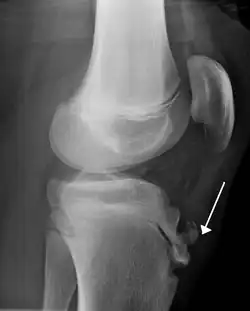

Lateral view X-ray of the knee demonstrating fragmentation of the tibial tubercle with overlying soft tissue swelling. | |

Risk factors include overuse, especially sports which involve frequent running or jumping.[3] The underlying mechanism is repeated tension on the growth plate of the upper tibia.[3] Diagnosis is typically based on the symptoms.[3] A plain X-ray may be either normal or show fragmentation in the attachment area.[3]